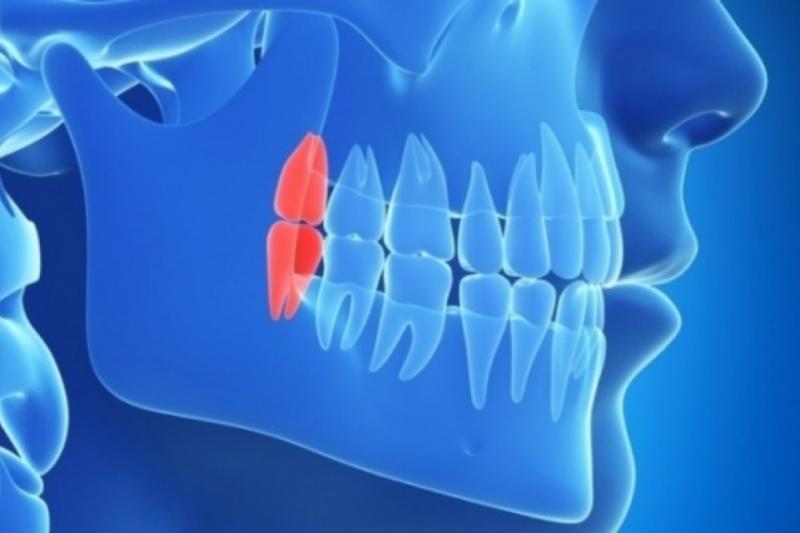

У зубов мудрости в абсолютном большинстве случаев имеется аномальное положение. Они не прорезываются или недопрорезываются до конца. Они становятся причиной воспаления десны в коронковой части зуба и других проблем. К тому же, как правило, такие зубы не смыкаются с аналогичными зубами на противоположной челюсти. При этом они давят на соседние, что приводит к скученности зубов.

И, пожалуй, самая большая проблема – это то, что из-за своего неправильного положения они плохо влияют на соседние вторые моляры, из -за чего приходится при самом плохом стечении обстоятельств удалять не только восьмые, но и седьмые зубы. Если после удаления восьмого зуба ничего делать не нужно – удалил и забыл, то седьмые зубы необходимы нам для полноценного жевания, поэтому их удаление приводит к последующим заботам – установке имплантатов.